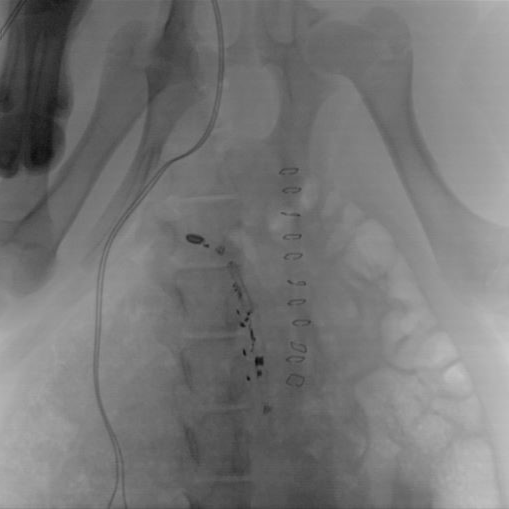

CT-Imaging

Image to verify placement of the sensor.